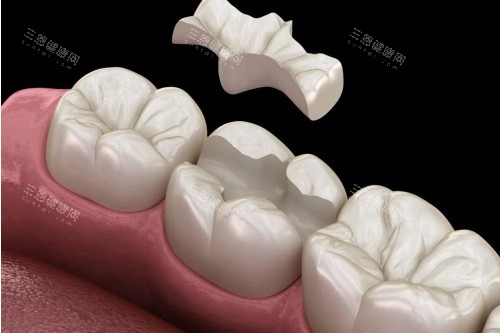

清理完蛀洞后,张医生给我看了几种补牙材料,有树脂的、玻璃材料的,还有进口的纳米树脂。他详细介绍了每种材料的优缺点:“树脂材料颜色和牙齿很接近,硬度也够,适合补后牙;玻璃材料对牙齿刺激小,适合儿童或者敏感牙;进口纳米树脂更耐磨,使用寿命更长。”他还根据我的情况推荐了树脂材料,说性价比较高,价格也在我的预算范围内。

选好材料后,张医生就开始填充了。他特别细致,填充完还会用工具一点点塑形,打磨,直到和我的牙齿形状完全贴合。补完后,他让我咬合几下,问我“有没有高低不平的感觉?”,调整到合适的高度后,又用光照固化,整个过程大概也就二十多分钟。